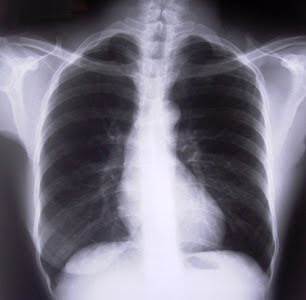

Aumenta la mortalidad por Enfermedad Pulmonar Obstructiva Crónica (EPOC)

La Enfermedad Pulmonar Obstructiva Crónica (EPOC) es una irreversible. Se caracteriza por la disminución del flujo de aire en los pulmones, que puede afectar tanto a hombres como a mujeres y que tiene entre sus principales factores de riesgo al tabaquismo, así como también la exposición prolongada e intensa a humo de leña, como se usa en algunos lugares del campo para cocinar o calefaccionar los ambientes.